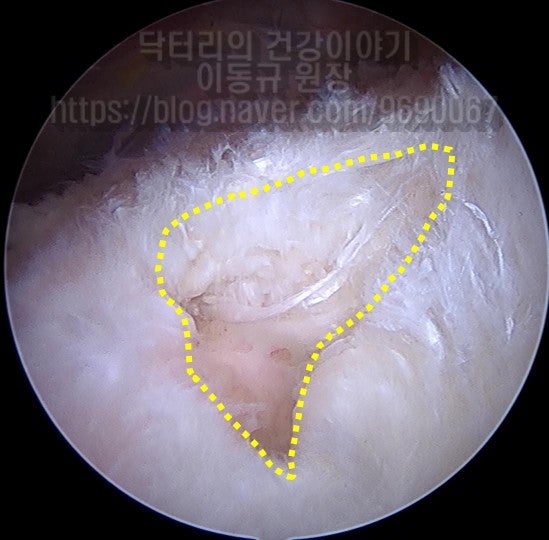

이 환자의 경우 나이가 비교적 젊음에도 불구하고 힘줄의 상태가 매우 좋지 않았습니다. 아마 수년간 통증주사(아마도 스테로이드)만 맞고 팔을 계속 사용하면서 회전근개 손상은 점점 진행되고 퇴행성 변화가 가속화 된 것으로 사료됩니다. 수술 후 6주에 MRI 검사를 시행하였습니다.